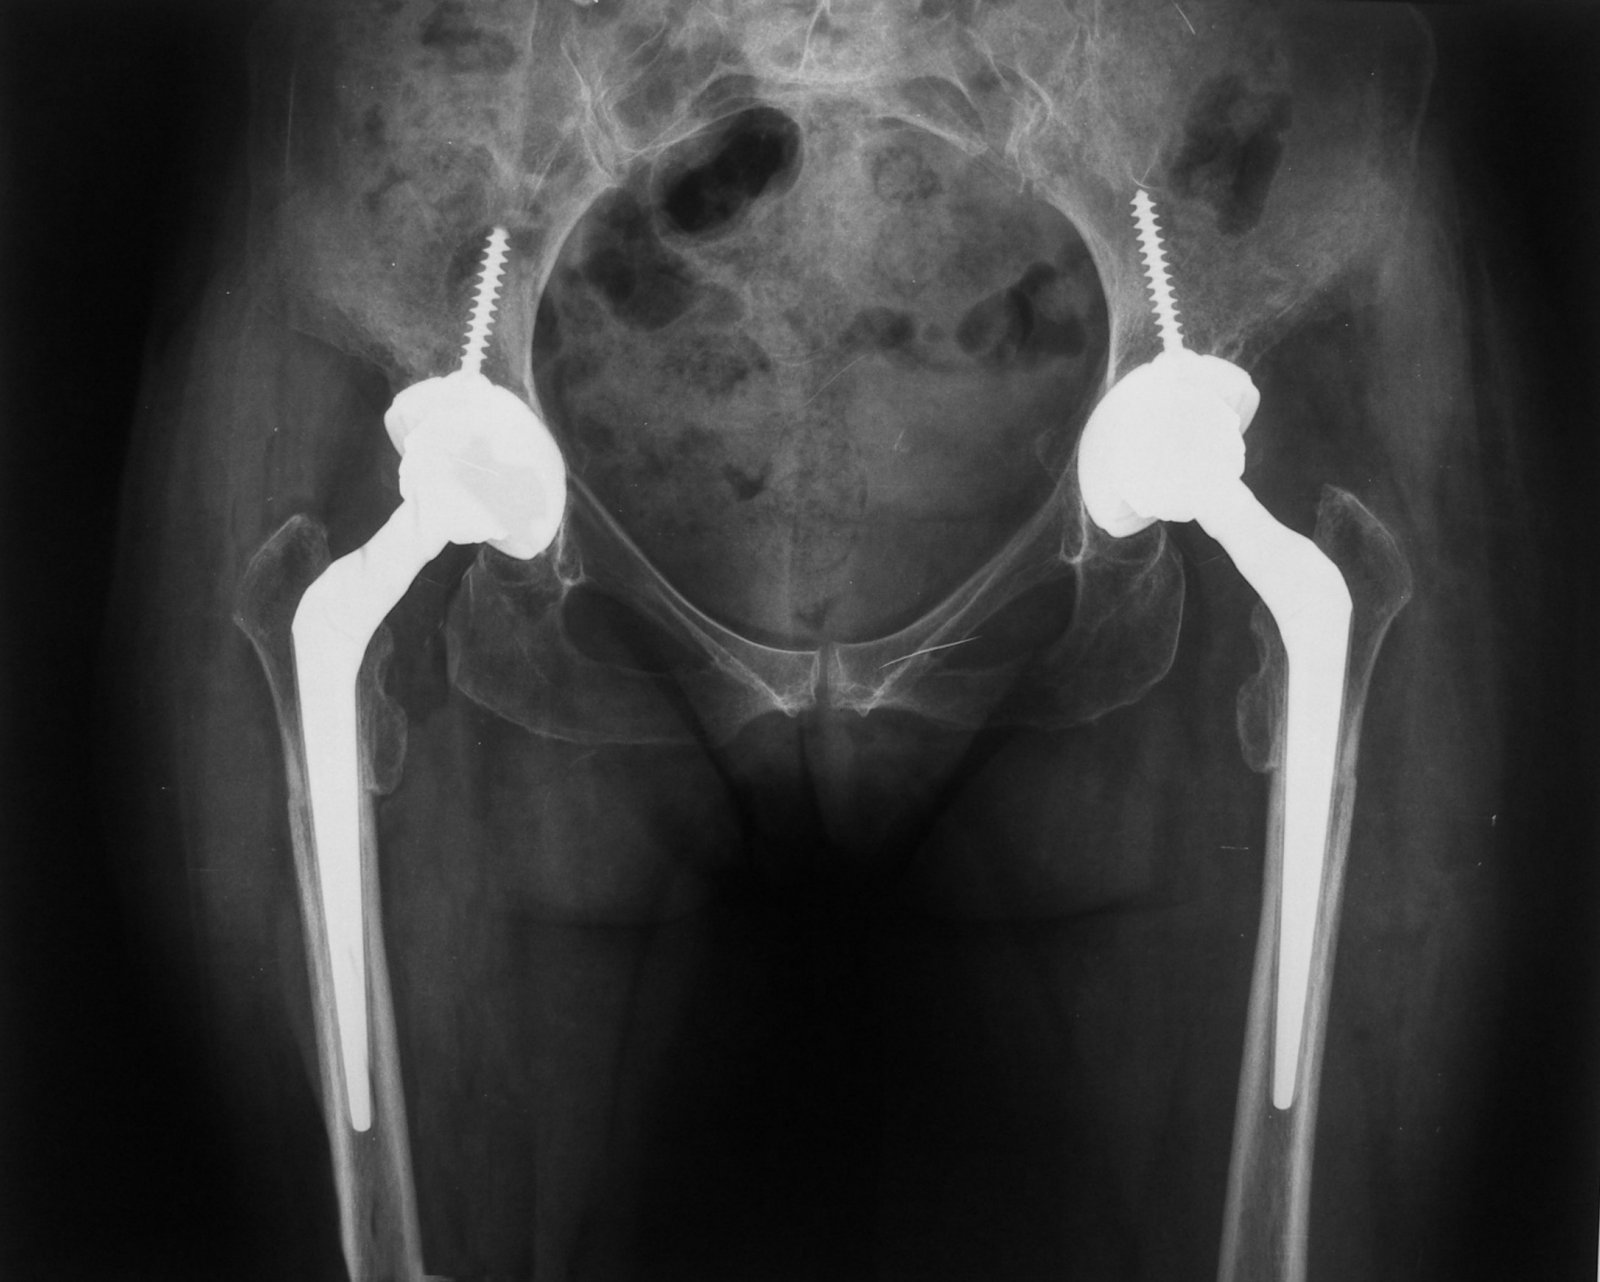

Controllo postoperatorio

Controllo a 6 mesi dal secondo intervento. Visibile a livello sottotrocanterico l’ osteotomia ormai consolidata. Ottimo il risultato clinico e funzionale. La paziente deambula senza Trendelenburg e senza dolore.

Verifica del rispetto degli indici di Pierchon

Elaborazione grafica di sovrapposizione della radiografia postoperatoria e della preoperatoria. Le protesi sono correttamente posizionate nel paleocotile. Gli indici di Pierchon sono corretti.